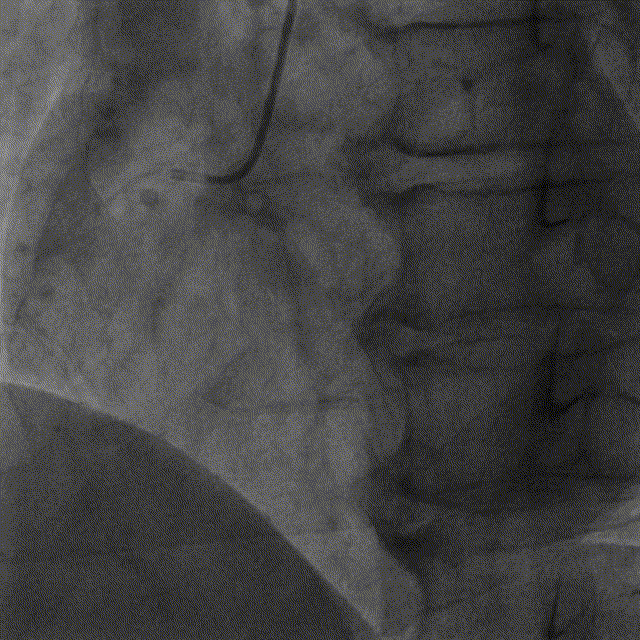

基于OCT的评估,钱菊英教授选取2.5*20mm的球囊对LAD病变进行预扩张,并植入2.5*38mm药物洗脱支架一枚,再选取2.5*15mm的高压球囊于支架内后扩张塑形。复查造影及OCT提示支LAD架贴壁及膨胀良好,手术效果满意。

LAD植入支架后OCT及造影图像

微创阿格斯™OCT提供的高质量图像帮助术者对病变进行精准化评估,基于OCT图像指导支架植入并检查支架即刻植入效果,保证了即刻手术效果,并降低了支架失败的风险。钱菊英教授特别强调,NOPURGE®成像导管在严重狭窄病变中展现出了优越通过性,同时NOPURGE®成像导管不再需要冲洗导管内腔,简化了操作流程,对PCI术者更为友好。